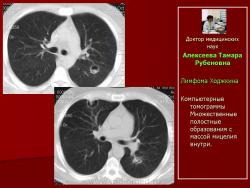

Следует отметить, что не всегда при туберкулезе легких отмечалась классическая скиологическая картина. Трудности в постановке диагноза туберкулеза возникали при появлении множественных полостных образований в легких с тонкими стенками на фоне неизмененной легочной ткани. В отдельных полостях определялись шаровидные массы, что заставило расценить выявленные в легких изменения как проявления аспергиллеза (рис. 7).

Рис. 7. Б-ного Р. Лимфома Ходжкина. В легочной ткани - полостные образования с шаровидным уплотнением внутри.

Однако при микроскопическом исследовании мокроты больного Р., страдающего лимфомой Ходжкина, были обнаружены микобактерии туберкулеза. На фоне противотуберкулезной терапии отмечена положительная динамика, а в дальнейшем и полная регрессия изменений в легких.

При полостной форме инвазивного аспергиллеза определялись разнокалиберные (от 0,8 - 4,5см. диаметром) единичные (рис. 18, 19) или множественные полостные образования, связанные с сосудами, имеющие пристеночные шаровидные массы внутри, окруженные полумесяцем. Отмечалось неравномерное утолщение стенок полостей на ограниченном участке или по всему периметру (рис. 20). Иногда вокруг полостных образований выявлялся симптом «ореола» вокруг и реакция прилежащих отделов плевры.

Рис. 20.Б-ной Т. Лимфома Ходжкина

Компьютерные томограммы Множественные полостные образования с массой мицелия внутри.

Следует отметить, что во всех наблюдениях полостные образования – аспергиллемы появлялись в неизмененной ранее легочной ткани.

Независимо от формы поражения нами отмечено, что при инвазивном аспергиллезе информативным признаком являлось наличие полостных образований.

Для другого оппортунистического микоза - аспергиллеза легких наиболее информативным рентгенологическим признаком являлось наличие полостных образований.Разнокалиберные (0,8 - 4,5см. диаметром) единичные или множественные полостные образования с пристеночными шаровидными массами внутри, окруженные полумесяцем и «ореолом» вокруг, развивались в неизмененной легочной ткани. Стенки полостей были неравномерно утолщены на ограниченном участке или по всему периметру. В ряде случаев имела местореакция прилежащей плевры.